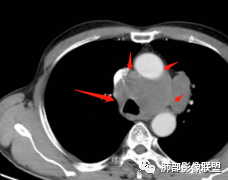

1.左肺门及纵隔见异常增大淋巴结,部分融合,不均匀轻度强化,未见明显坏死。

肿大淋巴结与纵隔血管等结构“无缝”贴合。

2.纵隔增宽但依旧居中。

1.这应当是常见的小细胞肺癌的转移方式。

别忘了,患者左肺上叶那个略显饱满的的小结节,有理由相信那是发源地。

因为这些符合肺癌的整个转移路径!

2、小细胞癌恶性程度高,发展迅速,转移发生早;常有纵隔淋巴结的明显增大融合(发生率达96.5%),呈“冰冻纵隔”,淋巴转移常为逐站的连续性转移;亦有血行转移,脑、肾上腺、肝、胰、骨髓等;转移灶常比原发灶大得多,即“娘小崽大”特点;